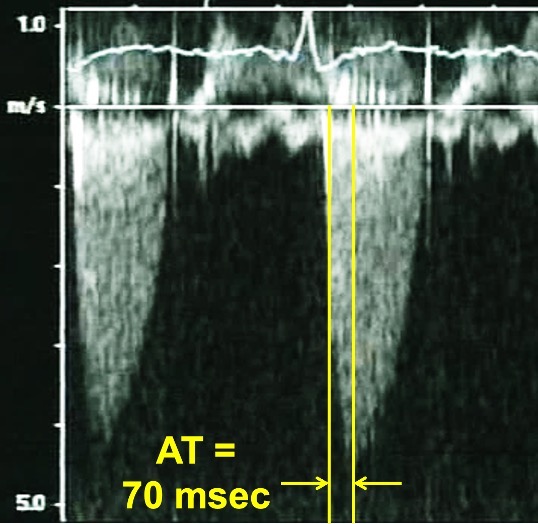

Progressive stenosis will lead to a prolonged acceleration time (AT), which is the time to the peak of the jet velocity as a result of delayed peaking of the velocity during systole. Therefore, the Doppler profile contour of an aortic prosthesis with stenosis with thrombi or pannus formation will be blunted and rounded as opposed to the triangular shape characteristic of a normally functioning prothesis (Figs. 4,5). This can be quantified by the ratio of the AT to the total ejection time (ET) over which blood flow occurs during systole, as a normal AT/ET ratio is less than 0.32. The AT as well as the AT/ET can also help distinguish true prosthetic obstruction from other conditions that confer a “functional” obstruction such due to high flow states (which can result from anemia, thyrotoxicosis, AV fistulas, or significant aortic regurgitation), pressure recovery, or patient prosthesis mismatch that can also lead to an elevated mean aortic prosthetic gradient. A functional obstruction will present with a peak velocity greater than 3 m/s, but the AT will be less than 80 ms, and the AT/ET, though it may be mildly elevated will not typically be greater than 0.37 [50, 51].

Fig. 5.Continuous Wave Doppler of an aortic prosthesis with structurally obstructive hemodynamics. Note the rounded contour of the Doppler jet, with an acceleration time (AT) of 160 msec.